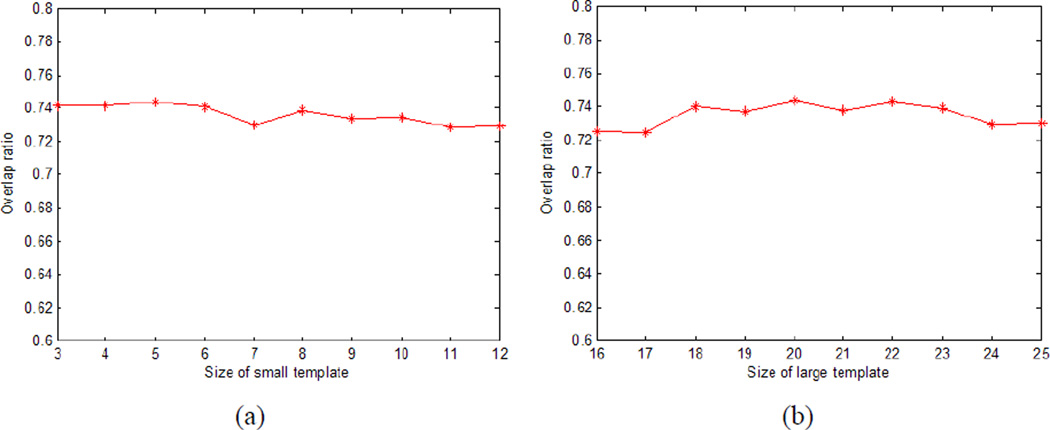

In the template matching (section 2.2), the size r is different for the small and large templates. Fig.11 shows the mean overlap ratio for different sizes of small (a) and large (b) templates. We varied the size of small template from 3 to 12, and the size of large template from 16 to 25. From Fig.11, we can see that the mean overlap is nearly constant with the different sizes of the templates, which means that our algorithm is relatively insensitive to the size of template.

Fig.11.

Mean overlap ratio for different sizes of small (a) and large (b) templates